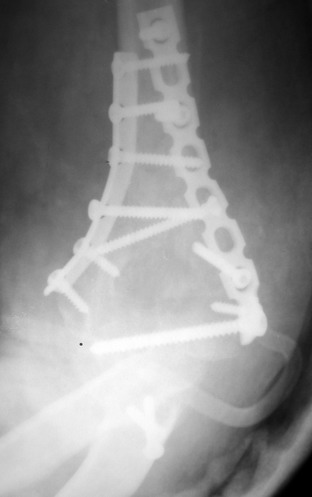

Djoldas Kuldjanov, M.D. 09 Сентябрь 2005, 20:07

Примерный случай, только перелом был открытый, в задне-медиальной стороне рана около 2 см по характеру "изнутри кнаружи", неврологический статус со слабостью сгибания мизинца, также слабая абдукция и аддукция указательного пальца и сгибания в кисти.

Больному сделали обработку и наложили временный аппарат внешной фиксации плечо-предплечье.

На шестой день сделали открытую репозицию чрезлоктевым доступом двумя locking plate, локтевой нерв был ушибленным, после операции положительная динамика в Flexor Carpi Ulnaris. Фиксацию локтевого отростка произвели tension band technique с дополнительным шурупом.

Этапы операции на снимках....